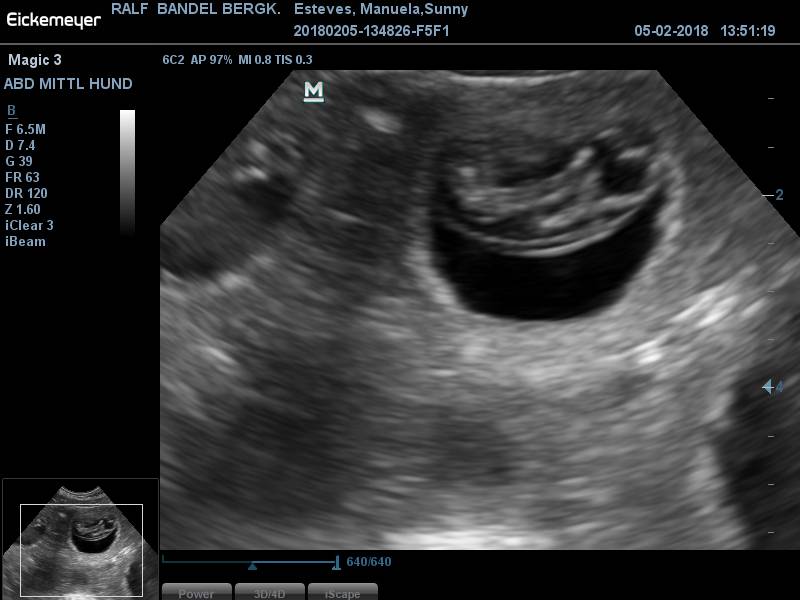

Am 05.02. wissen wir mehr --dann fahren wir zum Ultraschall !!!

Heute waren wir beim Ultraschall !!!--Und ja im Stehen wird geschaut und sofort werden wir fündig !!--Juhuhuhu !!!--Wie schön!!!Jedesmal ein kleines Wunder!!!-Dann schauen wir uns eine Frucht noch genau an und können Kopf ;Beinchen und sogar den Herzschlag sehen --wahnsinn !!!Einfach genial !! Total happy --als würde ich selber Mutter fahren wir wieder nach Hause.Danke Sunny und Dexter!!Wunderschön!!!